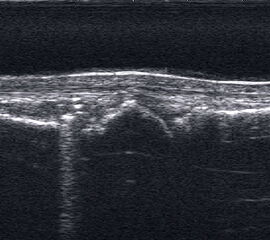

Fibulaverletzung beim Erwachsenen

Fibulafraktur mit Unterbrechung der Kortikalis und Hämatom.

Abbildung 13

Lagerung: Rückenlage, leichte Innrotation des Fußes.

Schnittebene: LS über distaler Fibula.

Referenzstruktur: Fibula im Längsverlauf.

Befunde: Bei einer Außenknöchelfraktur ist eine Unterbrechung der echogenen metaphysären Knochenlinie mit umgebendem flachen, echoarmen periostalen Hämatom zu sehen (Abb.13).

Cave: Ein Os subfibulare kann ebenfalls fälschlicherweise als Fibulaverletzung interpretiert werden!